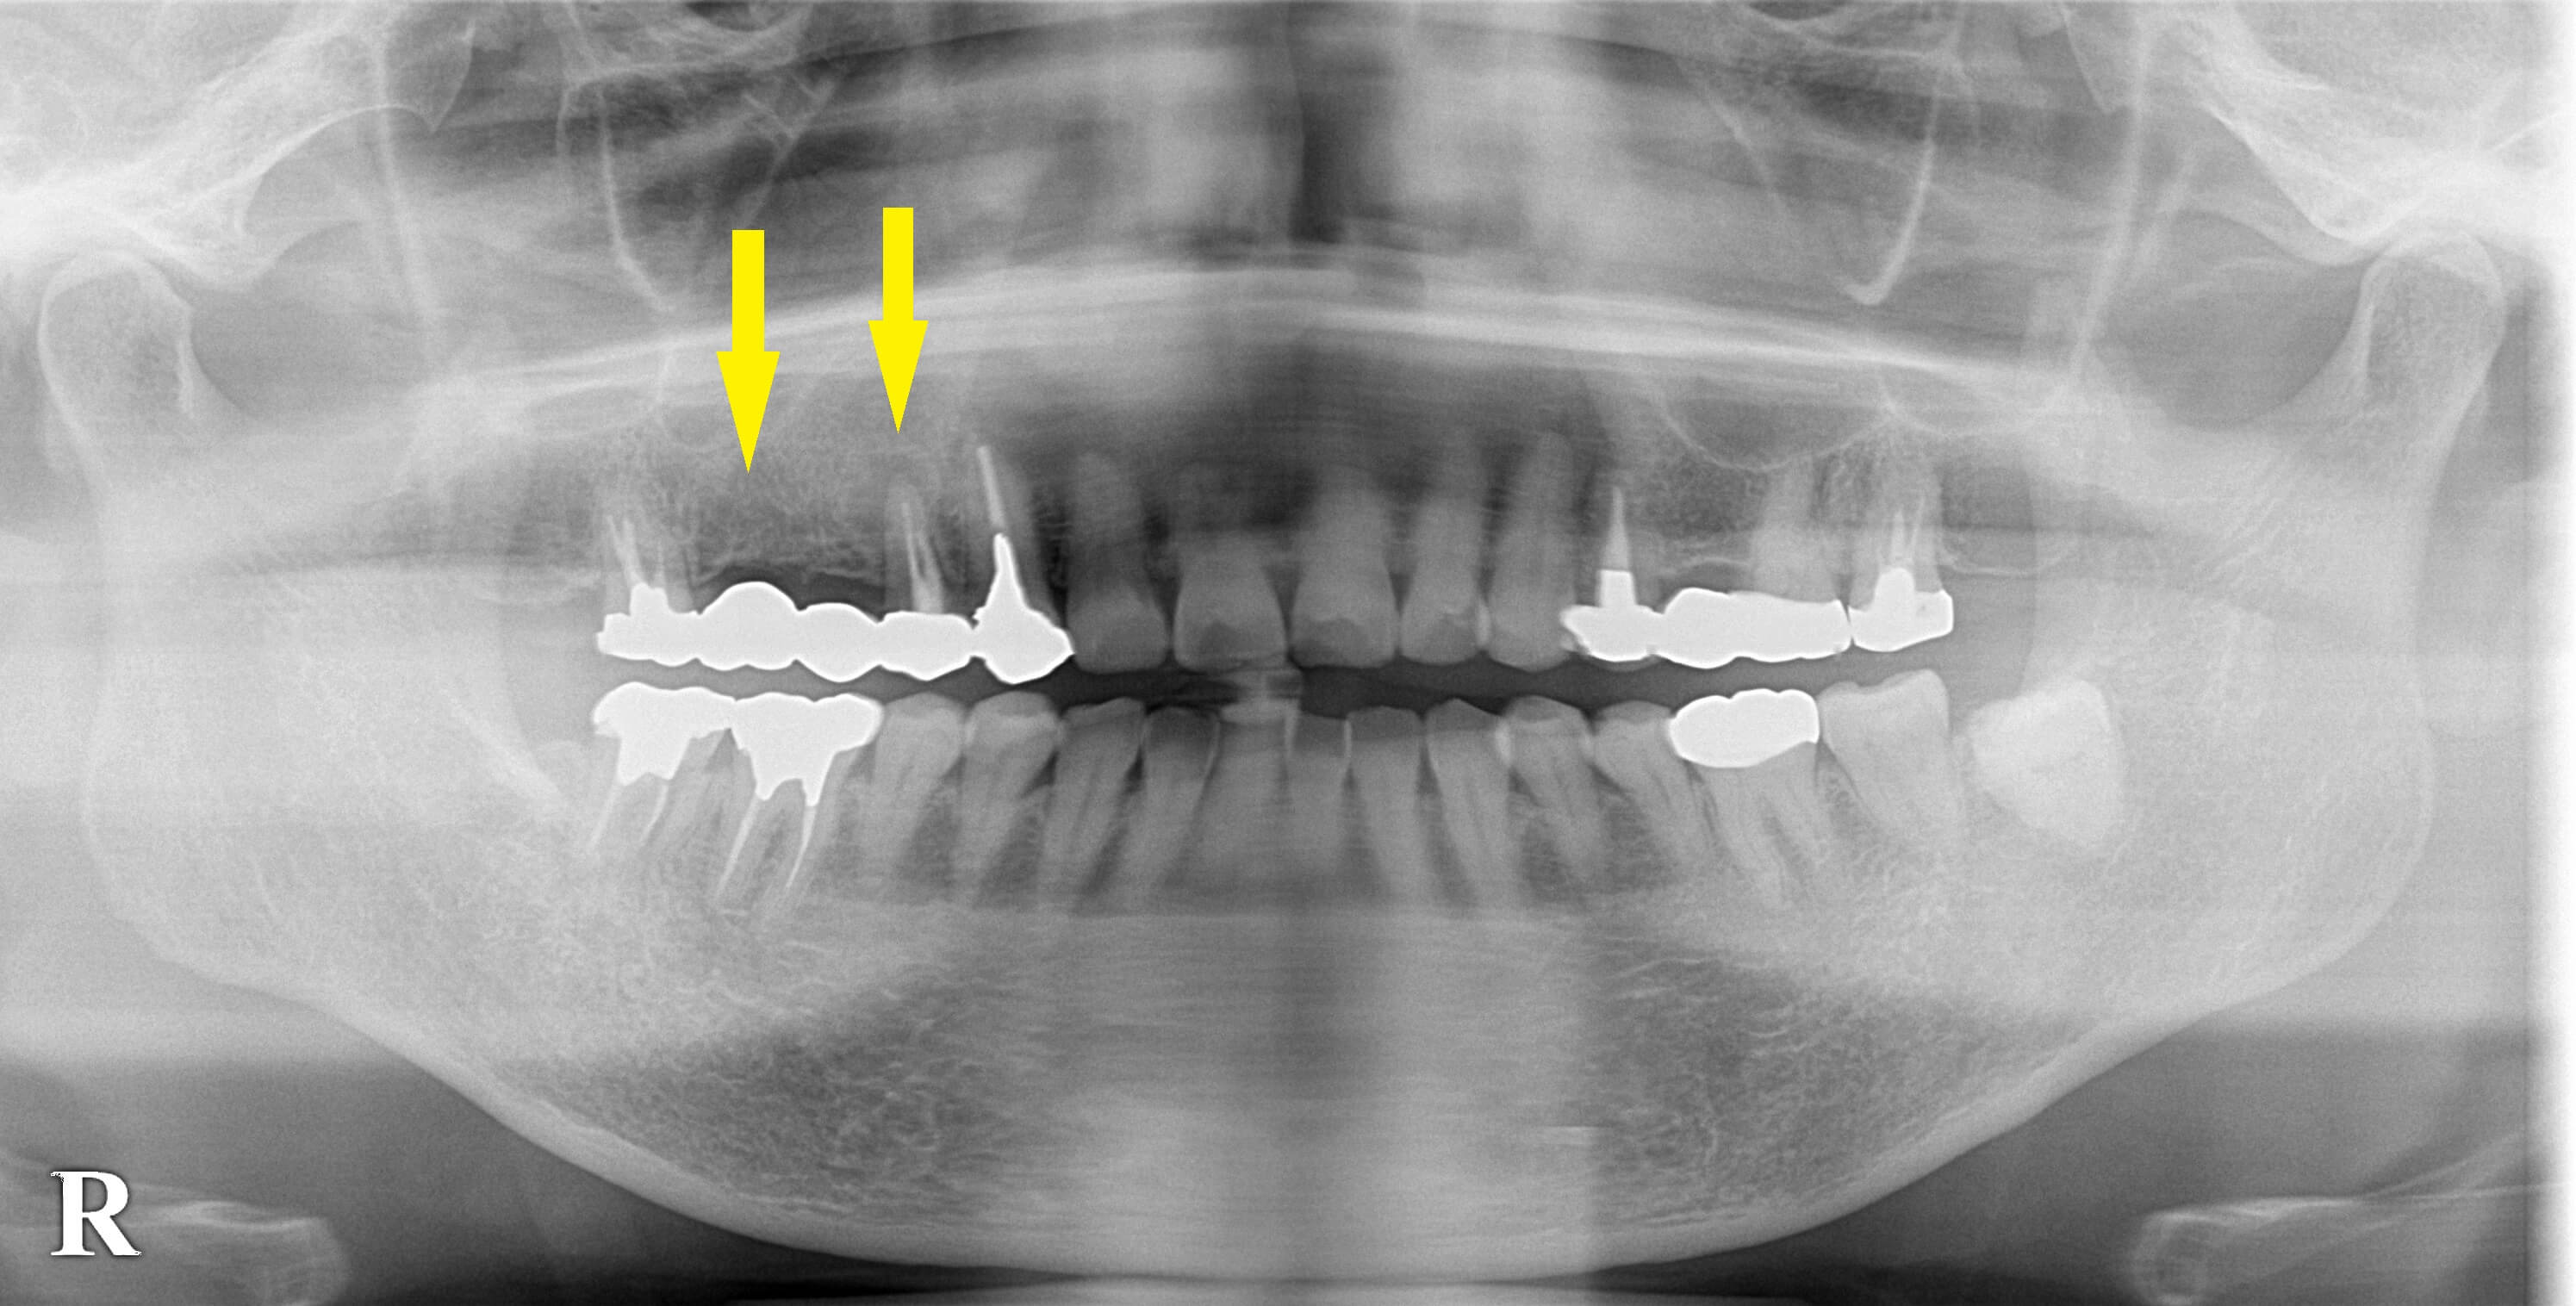

右上顎にブリッジが装着されていたのですが、支えになっている前方の歯が破折してきてしまいブリッジが外れてしまったそうです。

CTを撮ってみると、破折した歯の周囲は骨がかなり吸収されており、状態は良くありませんでした(下の写真上段右)。

この状態でも、なんとか抜歯してそのままインプラントを埋入する、抜歯即時埋入が可能と考え、

この部位と、その後方にもう1本インプラントを埋入して、インプラントで3歯のブリッジを行う治療計画としました。

下の写真中段が手術前のCT、下段が手術後のCTです。